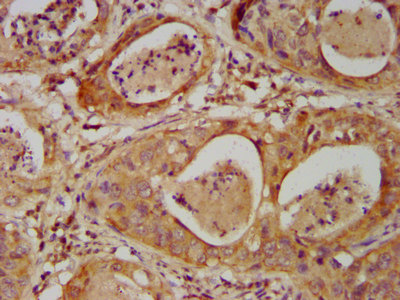

IHC image of CSB-PA621761LA01HU diluted at 1:500 and staining in paraffin-embedded human cervical cancer performed on a Leica BondTM system. After dewaxing and hydration, antigen retrieval was mediated by high pressure in a citrate buffer (pH 6.0). Section was blocked with 10% normal goat serum 30min at RT. Then primary antibody (1% BSA) was incubated at 4°C overnight. The primary is detected by a biotinylated secondary antibody and visualized using an HRP conjugated SP system.

IHC image of CSB-PA621761LA01HU diluted at 1:500 and staining in paraffin-embedded human colon cancer performed on a Leica BondTM system. After dewaxing and hydration, antigen retrieval was mediated by high pressure in a citrate buffer (pH 6.0). Section was blocked with 10% normal goat serum 30min at RT. Then primary antibody (1% BSA) was incubated at 4°C overnight. The primary is detected by a biotinylated secondary antibody and visualized using an HRP conjugated SP system.